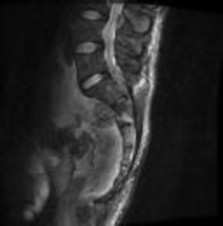

Figures 1 through 3 show sagittal and axial MRIs and a radiograph from a

77-year-old woman with leg pain when standing and walking of 1 year duration. The pain improves when she leans forward. She has been in physical therapy, taken oral analgesics, and had epidural injections with minimal relief. What is the best next step?

4. Microdiskectomy Discussion: B

The patient has lumbar stenosis of L2-3 and L3-4. She has no spondylolisthesis or instability. For her condition, spinal fusion plays a minimal role. She has no evidence of instability, and her condition can be addressed through laminectomy only. No role exists for microdiskectomy, because her disease results from a combination of ligamentum flavum hypertrophy and facet hypertrophy.